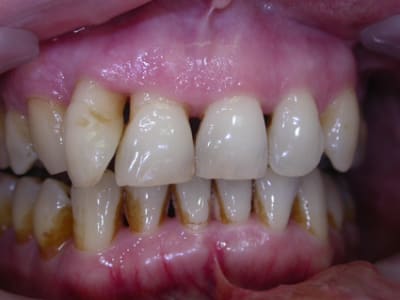

d'abord faudrait des photos ou des radios ..

la persistance de problèmes s'accompagne de quels signes ?

car il ne faut pas confondre la cause du problème qui est essentielllement à base infectieuse sur un terrain peut être prédisposé et la consequence du problème qui est la perte osseuse la presence de poches etc ... .....

si tu traites la cause tu gueriras l'infection mais il te restera peut être des sequelles ( pertes osseuses par exemple )